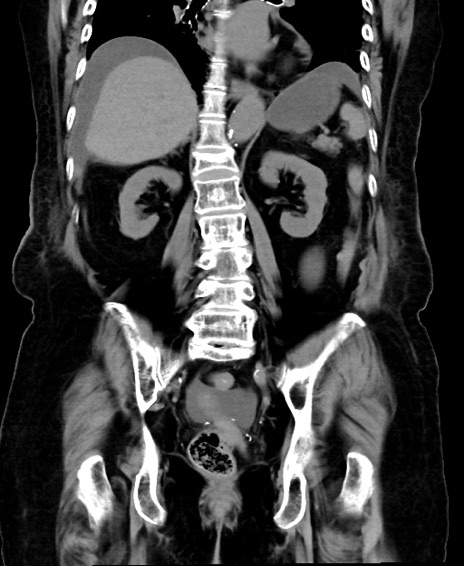

症例40(冠状断像)他院1日前

冠状断像